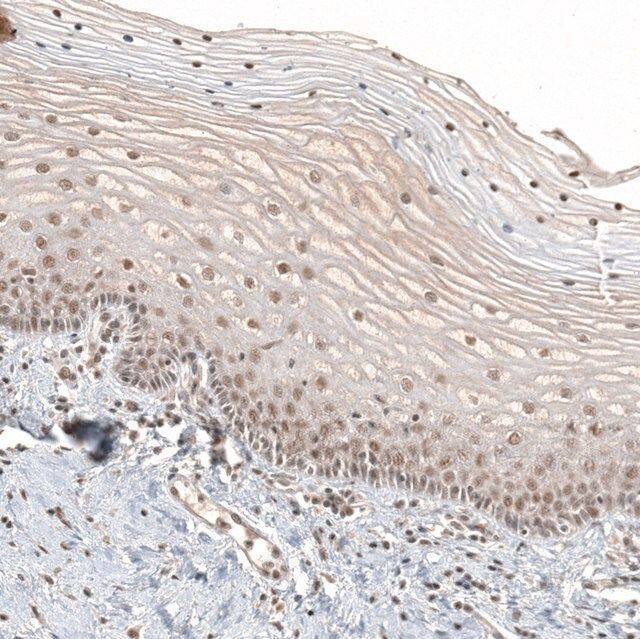

The Human Protein Atlas project can be subdivided into three efforts: Human Tissue Atlas, Cancer Atlas, and Human Cell Atlas. The antibodies that have been generated in support of the Tissue and Cancer Atlas projects have been tested by immunohistochemistry against hundreds of normal and disease tissues and through the recent efforts of the Human Cell Atlas project, many have been characterized by immunofluorescence to map the human proteome not only at the tissue level but now at the subcellular level. These images and the collection of this vast data set can be viewed on the Human Protein Atlas (HPA) site by clicking on the Image Gallery link. To view these protocols and other useful information about Prestige Antibodies and the HPA, visit sigma.com/prestige.

| technique(s) | immunoblotting: 0.04-0.4 μg/mL immunohistochemistry: 1:500-1:1000 |